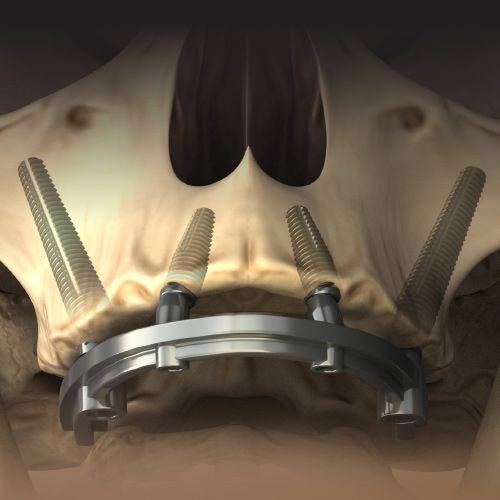

Dental Rehabilitation of the Atrophic Maxilla

Ankur Johri, DDS, MD, FACS

Friday, July 29, 2022

This Compendium eBook features a continuing education (CE) article presents important diagnostic and treatment planning principles of the All-on-4 treatment concept for the rehabilitation of the atrophic maxillary arch, and includes a case report illustrating free-hand implant placement using this treatment approach.